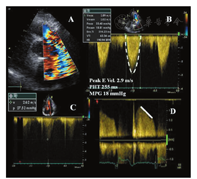

在大部分功能正常的双叶机械性PHV,其二尖瓣前向血流舒张早期峰值速率(E峰)<1.9 m/s,但在小的不匹配的人工瓣可高达2.4 m/s[90,152,153,154]。正常二尖瓣平均跨瓣压差通常<5~6 mmHg[155]。二尖瓣跨瓣血流速度和压差随狭窄程度的加重而增加。然而,人工瓣的大小、心室和心房功能、心腔的顺应性、相对的心腔压力、存在PPM或任何梗阻都可以影响跨瓣血流速度。心动过速时导致舒张期充盈时间缩短和E峰速度增加[19]。同样地,显著的二尖瓣反流引起容量负荷增加进而导致二尖瓣跨瓣血流速度增加。所有这些情况均强调了对同一患者需要进行系列随访和测量比较的必要性[14]。如果排除了上述情况,E峰速度≥2.5 m/s和二尖瓣平均跨瓣压差≥10 mmHg提示存在重度人工二尖瓣梗阻[14]。二尖瓣PHV明显梗阻的患者在负荷超声心动图时其跨瓣平均压差增加(≥12 mmHg)(图23)[36,138]。与术后即刻测量值相比发生变化时亦支持获得性PHV梗阻的诊断。在相似的心率下平均压差的增幅>5 mmHg提示存在瓣膜梗阻。

二尖瓣PHV功能正常时PHT常常<130 ms,而系列超声心动图检查PHT>200 ms则提示出现了显著狭窄。由于PHT受心率、LA和LV顺应性的影响,在心动过速或房室顺应性减低的患者,尽管存在显著人工瓣膜狭窄,其PHT仍显示为正常。在一度房室传导阻滞E峰和A峰融合时或舒张期充盈时间缩短的情况下不应测量PHT。对PHT轻度增加(130~200 ms)应谨慎解读[152,154]。

EOA和DVI(VTIPrV/VTILVOT)较少受血流的影响。EOA由连续性方程(每搏量/VTIPrV)计算得出,在合并轻度以上MR或AR时是不可靠的。在存在AR时,可用RVOT代替LVOT进行测量。相反地,由PHT推导计算的EOA在人工二尖瓣中是不适用的[106,111]。需要在排除AR的前提下对DVI进行正确解读。尽管测量值需要参照不同类型与型号的人工瓣膜的正常值,但EOA<1 cm2和DVI>2.5时须高度怀疑二尖瓣PHV存在明显梗阻[14]。

二尖瓣PHV梗阻的超声心动图评价应结合二尖瓣的2D/3D图像数据和定性、定量瓣膜梗阻程度的多普勒测量进行综合判断(图24)。必要时亦可选择其他影像学技术来评价瓣膜运动、结构和功能。例如,在无症状性人工瓣血栓形成的情况下,多普勒压差正常或仅轻度升高,需要借助荧光透视成像或心脏CT技术来识别双叶式人工二尖瓣异常的碟瓣运动[46]。数据的解读需根据瓣膜置换的时间、人工瓣的特点和血流动力学状态来进行。表15列出了评价二尖瓣PHV功能的影像学参数。当所有参数都正常时瓣膜功能异常的可能性非常低,而当大部分参数异常时PHV功能异常的可能性就很大[152]。